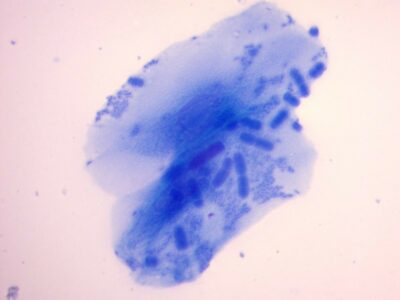

anaplasma inclusions

anaplasma inclusions -

anaplasma inclusions

anaplasma inclusions -